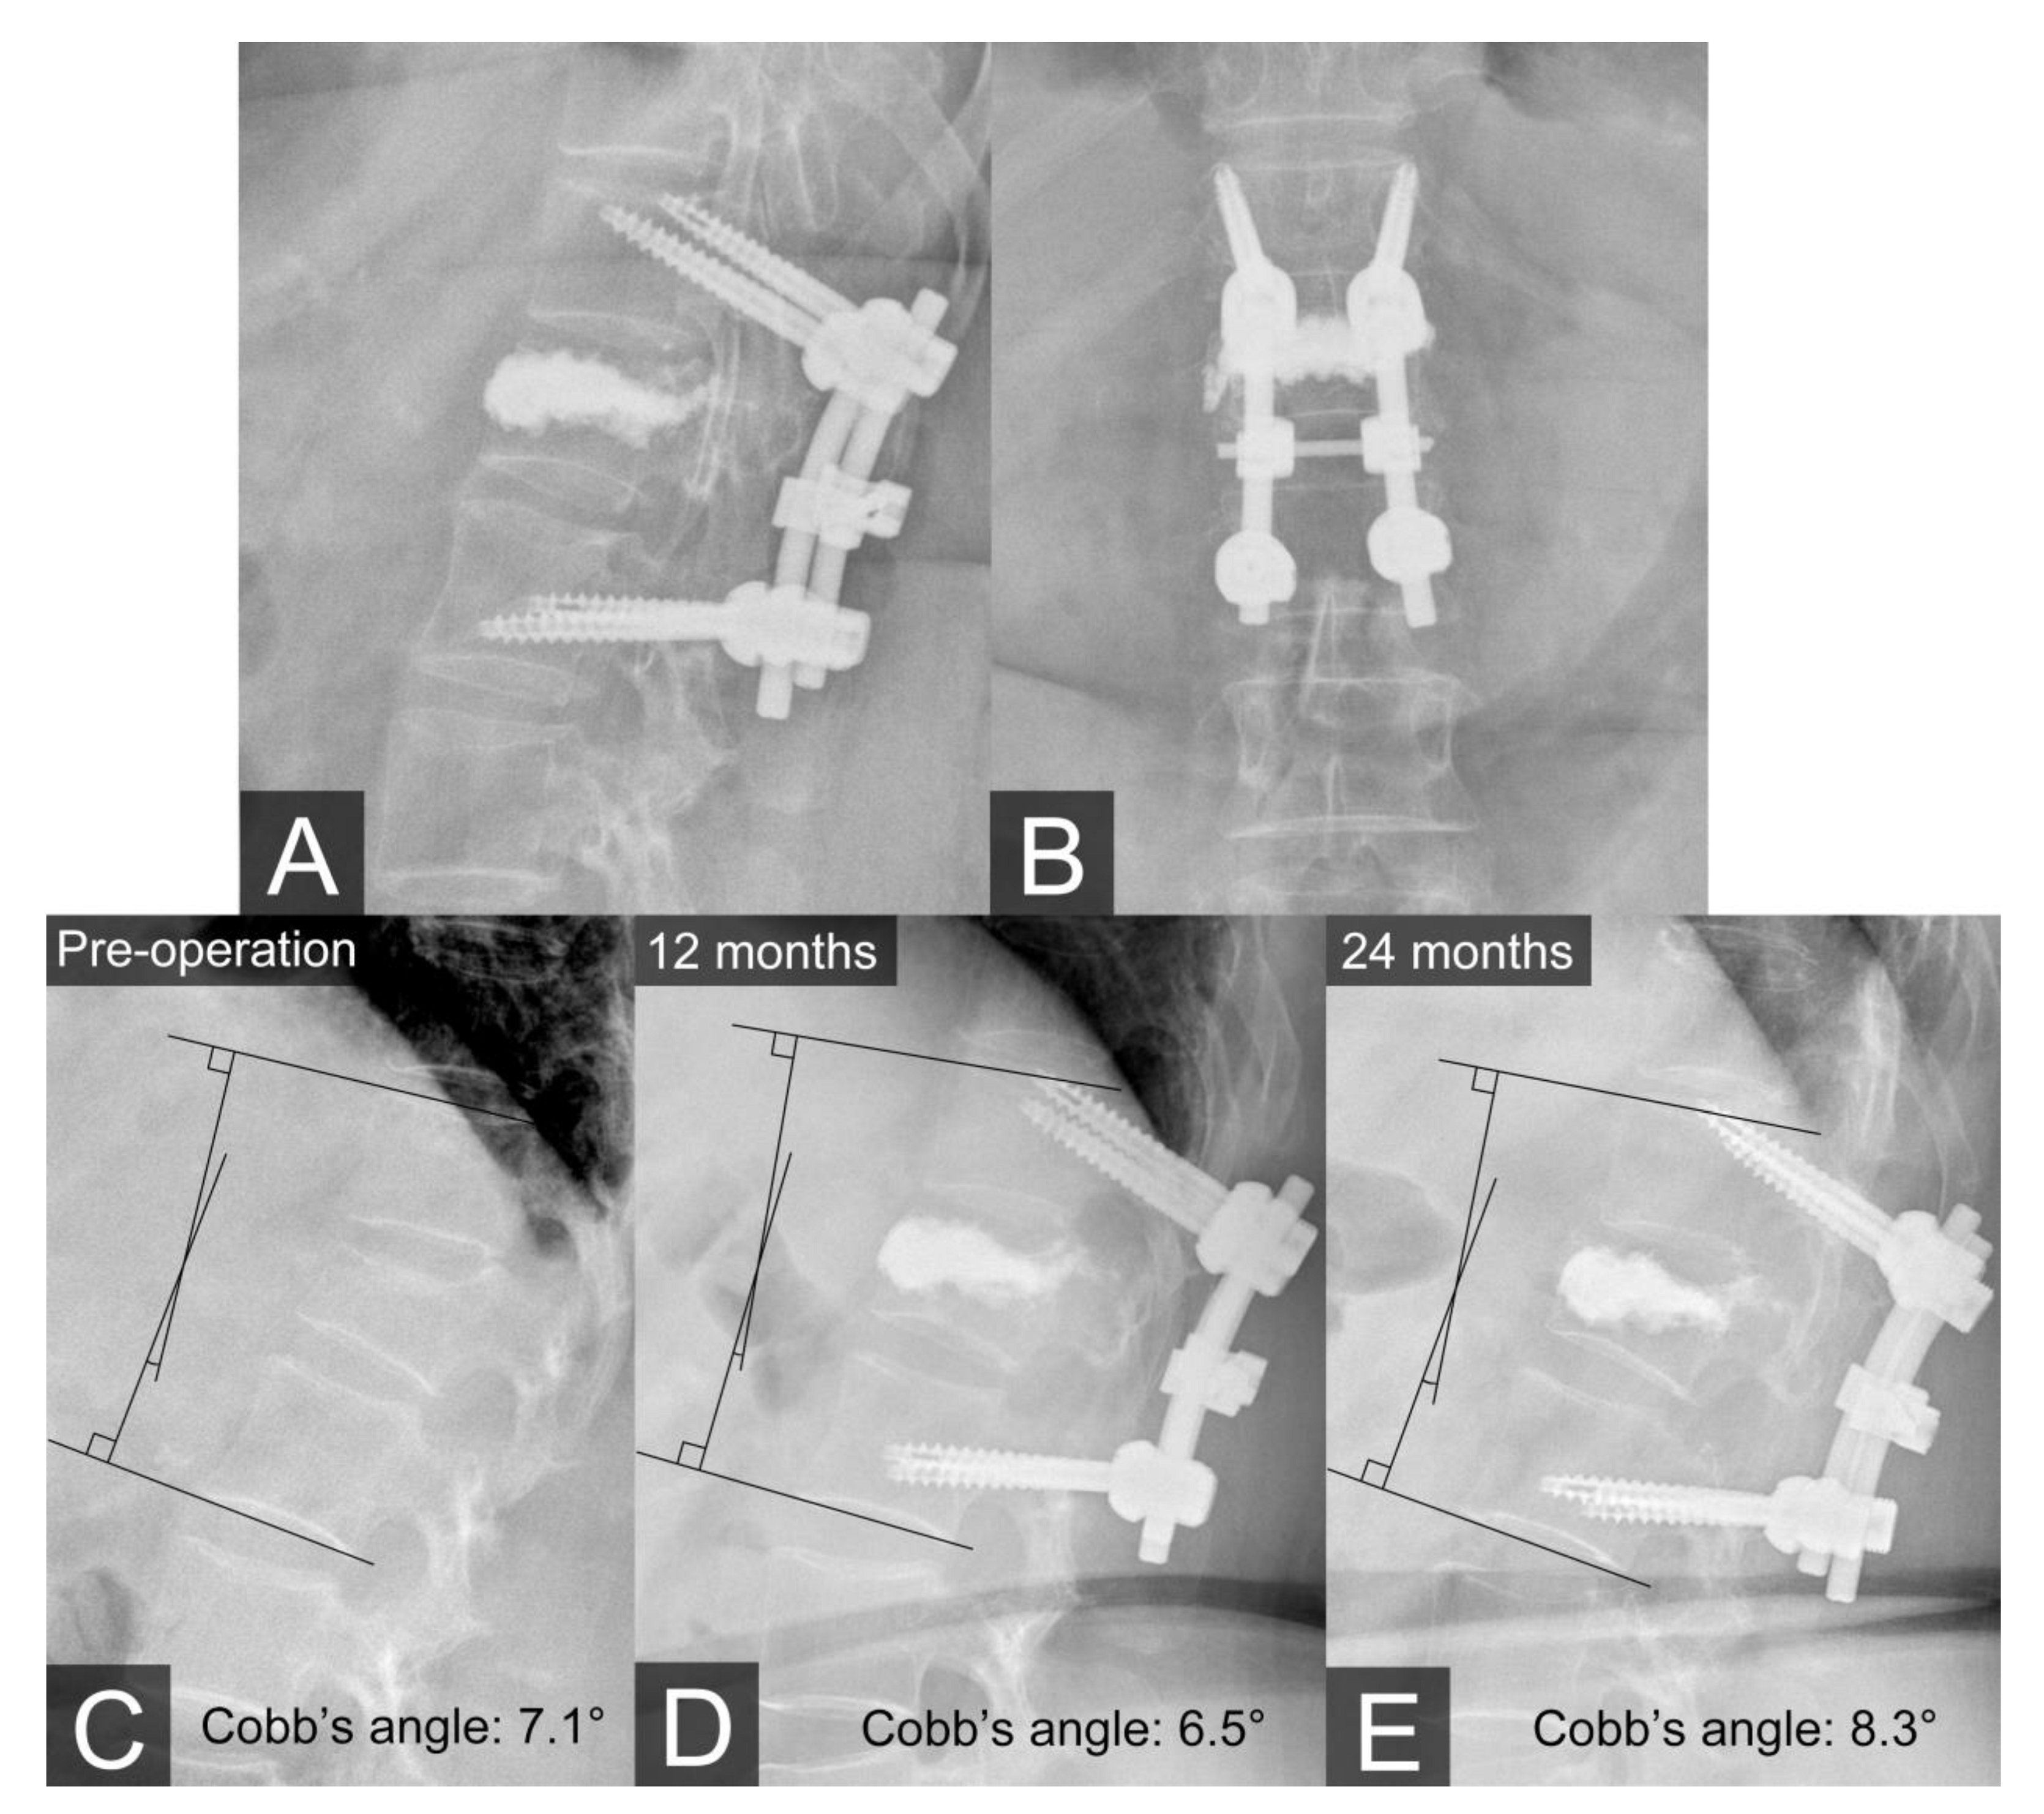

Lumbar spine plain films were acquired the day after surgery (Figure 3A,B), and at 1, 6, 12, and 24 months postoperatively. After the surgery, the patient’s VAS score improved from 8 to 2, and she regained her ambulatory ability. At the 24-month follow-up evaluation, the patient showed no obvious changes in the kyphotic sagittal Cobb’s angle nor was there any indication of instrument loosening (Figure 3C–E).

Figure 3.

(A,B) Plain films on the first day after the operation. (C–E) Plain films showing the kyphotic sagittal Cobb’s angle preoperatively and at 12 months and 24 months postoperatively. There was no obvious change in the kyphotic sagittal Cobb’s angle or evidence that the screws loosened at the 24-month follow-up evaluation.